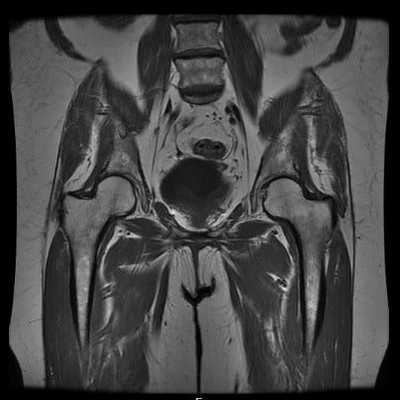

МРТ таза во фронтальной проекции в норме

Первая из 24 фронтальных МР-томограмм таза, полученных от задней поверхности к передней. На этой томограмме легко определяется широкая протяженность большой ягодичной мышцы. Визуализируется грушевидная мышца, берущая начало от передней поверхности крестца. Седалищный нерв лежит по ее переднему краю. Нижние ягодичные сосуды сопровождают седалищный нерв. Сосуды расположены медиальнее нерва. Полусухожильная мышца и длинная головка двуглавой мышцы бедра имеют общее сухожилие, отходящее от заднего отдела седалищного бугра. Сухожилие полуперепончатой мышцы начинается немного более кпереди и латеральнее. Крестцово-подвздошное сочленение в верхнем отделе представлено синдесмозом с небольшим синовиальным расширением кпереди. В более нижнем отделе сочленение представлено синовиальным суставом, однако здесь все еще визуализируются мощные дорзальные межкостные связки. Наиболее крупной структурой в заднем отделе бедра является большая приводящая мышца. Тонкая мышца занимает на бедре наиболее медиальное положение. Обширную зону наружного отдела бедра занимает латеральная широкая мышца. Широкая, почти горизонтальная квадратная мышца бедра визуализируется на протяжении от седалищного бугра до задней поверхности бедренной кости. На этом срезе визуализируется имеющая изогнутый контур синовиальная часть крестцово-подвздошного сочленения (КПС). Подвздошно-поясничная связка проходит от поперечного отростка позвонка L5 к подвздошной кости. Отрывное повреждение поперечного отростка этой связкой является ценным признаком задней нестабильности таза. Наружная запирательная мышца визуализируется почти на всем протяжении от своего начала в запирательном отверстии до места прикрепления в грушевидной ямке. От внутренней запирательной мышцы ее отделяет запирательная мембрана. Теперь срезы проходят через толщу приводящих мышц. Большая приводящая мышца имеет две головки. Короткая верхняя головка, показанная здесь, называется иногда малой приводящей мышцей. Она проходит от седалищно-лобковой ветви к заднему отделу бедренной кости. На этом срезе начинают визуализироваться приводящие мышцы. Из всех приводящих мышц, гребенчатая имеет наиболее верхнее прикрепление к заднему отделу бедренной кости. Визуализируются сегменты глубоких бедренных сосудов. Обратите внимание на взаиморасположение крупных сосудов бедра. Большая подкожная вена расположена с медиальной стороны в толще подкожно-жировой клетчатки. Поверхностные бедренные сосуды расположены медиальнее глубоких сосудов бедра. Сухожилие средней ягодичной мышцы прикрепляется к латеральной поверхности большого вертела. Большая ягодичная мышца проходит дистальнее и прикрепляется к подвздошно-большеберцовому тракту, фасции латеральной широкой мышцы бедра и задней поверхности бедренной кости. Бедренный нерв лежит между подвздошной и поясничной мышцами в подвздошно-поясничной борозде. Визуализируется прикрепление средней ягодичной мышцы к латеральному краю большого вертела. Малая ягодичная мышца прикрепляется более кпереди к переднему краю большого вертела. Внутренняя и наружная запирательные мышцы разделены жировой тканью запирательного отверстия. Сухожилие малой ягодичной мышцы прикрепляется к передней поверхности большого вертела. Общие бедренные сосуды разделились на глубокие и поверхностные. Общие бедренные сосуды проходят по передней поверхности длинной приводящей мышцы, которая формирует дно бедренного треугольника. Точка пересечения портняжной и длинной приводящей мышц образует вершину бедренного треугольника. От этого уровня и ниже сосуды проходят в приводящем канале. Путь сосудов через канал можно увидеть на более задних срезах. Напрягатель широкой фасции бедра расположен по переднему краю подвздошно-большеберцового тракта. Лобковый симфиз является сочленением передних отделов таза. Передняя головка прямой мышцы бедра берет начало от передней нижней подвздошной ости, в то время как задняя головка начинается непосредственно выше вертлужной впадины. Наружные подвздошные сосуды проходят на бедро медиальнее подвздошно-поясничной мышцы. После прохождения под паховой связкой эти сосуды становятся общими бедренными. Бедренный нерв является наиболее латеральной структурой, входящей в бедренный треугольник. На этой томограмме он не идентифицируется. На данном срезе хорошо визуализируется место впадения большой подкожной вены в общую бедренную вену. Наружные подвздошные сосуды становятся общими бедренными после прохождения позади паховой связки. Возле места своего прикрепления к лонному бугорку визуализируется короткий сегмент паховой связки. Лимфатические узлы представляют собой наиболее латеральные структуры у входа в бедренный треугольник. Портняжная мышца и прямая мышца бедра занимают наиболее переднее положение среди мышц бедра. Портняжная мышца проходит по диагонали от места начала в области передней верхней подвздошной ости к точке прикрепления в качестве части гусиной лапки на медиальной поверхности большеберцовой кости. Передний отдел бедра имеет богатую лимфатическую сеть. По средней линии визуализируется парная прямая мышца живота. Мышца начинается (не прикрепляется) от верхней ветви лобковой кости и гребня лобковой кости.